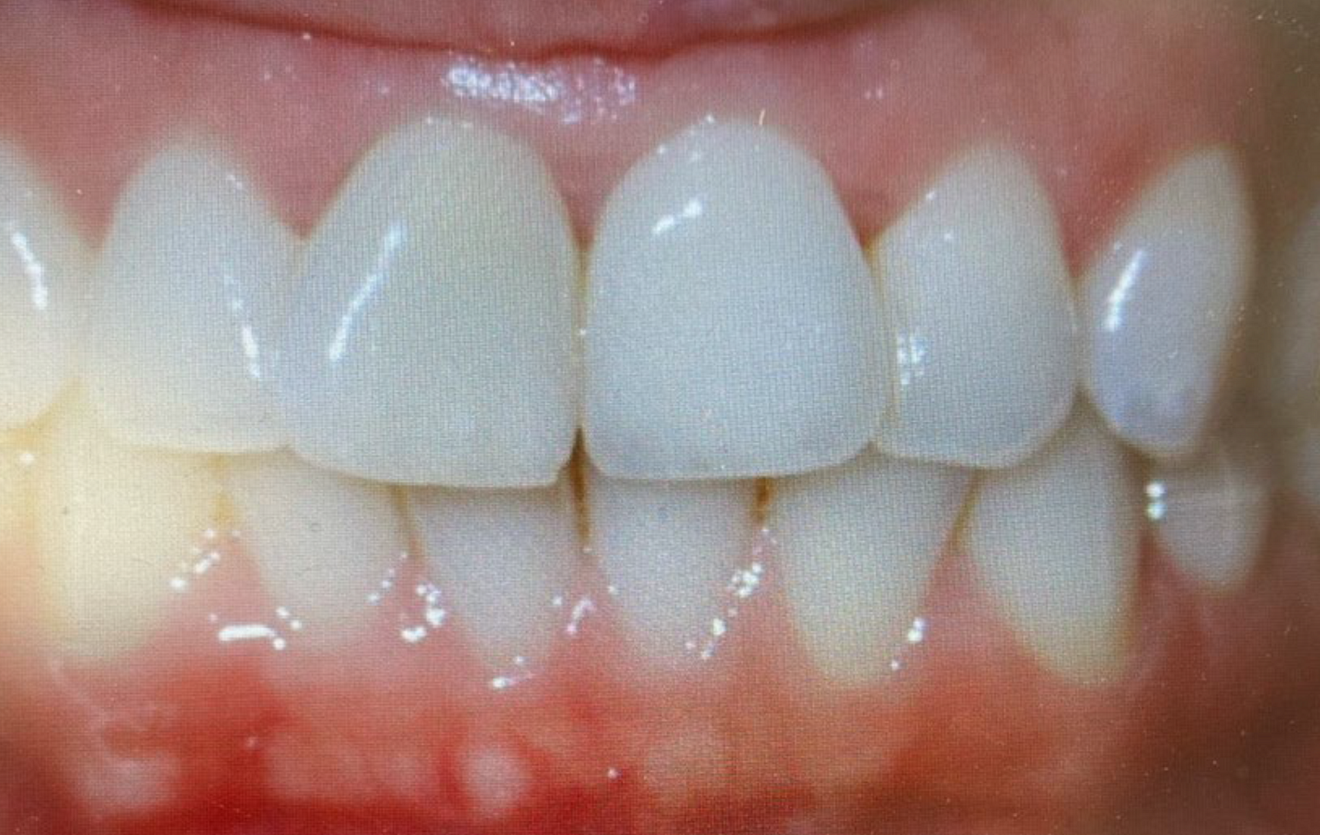

Fig. 1a: NobelProcera abutment designs in the study. NobelProcera full-contour/cutback zirconia implant crown (n = 105).

It is a very stable and well-tested solution for us. In our study, we’ve investigated over 460 abutments across a wide range of implant types, all from Nobel Biocare, and a wide range of abutment types as well: NobelProcera ASC, titanium, zirconia, full-contour (Figs. 1a–d & 2a–h).

Figs. 2a–h: Demonstration of the study results through the case of a non-smoking 34-year-old female patient with a missing maxillary central incisor. Radiograph (a)...